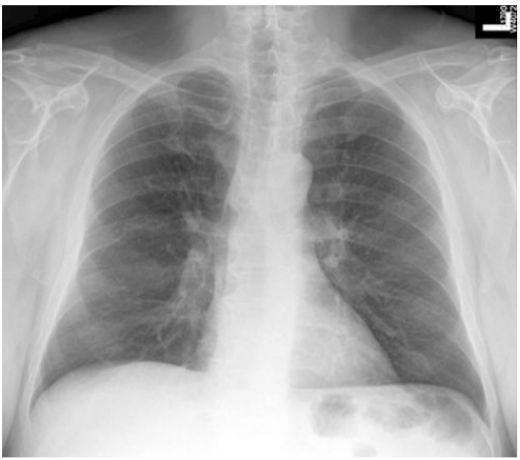

15. 50歲男性,患有糖尿病,胰臟癌及恐慌症,因突發性呼吸困難至急診求診。病患並無明顯胸痛或冒冷汗,意識清楚但情緒緊張,理學檢查發現體溫36.5℃,血壓 145/95 mmHg,脈博112/min節律規則, 呼吸 24/min快且深;四肢冰冷有輕微發紺現象。頸靜脈壓12 cm H2O,無明顯心雜音。呼吸音雙側正常,腹部平坦無壓痛,四肢活動正常亦無水腫。護理人員給予脈衝血氧定量計 (pulse oximeter) 偵測發現SpO2 84%,急診醫師隨即指示使用Venturi mask O2 35%。約半小時後,病人自覺症狀略為減緩,此時之動脈氣體分析: PH 7.50, PaO2 70mmHg, PaCO2 25 mmHg, HCO3 23 mEq/L, one touch blood glucose 320 mg/dl. EKG除竇性頻脈外其餘正常,胸部Ⅹ光如附圖,下列診斷何者最有可能? (A) Acute pulmonary embolism (B) Panic disorder related hyperventilation syndrome (C) Diabetic ketoacidosis (D) Endobronchial foreign body (E) Bronchial asthma